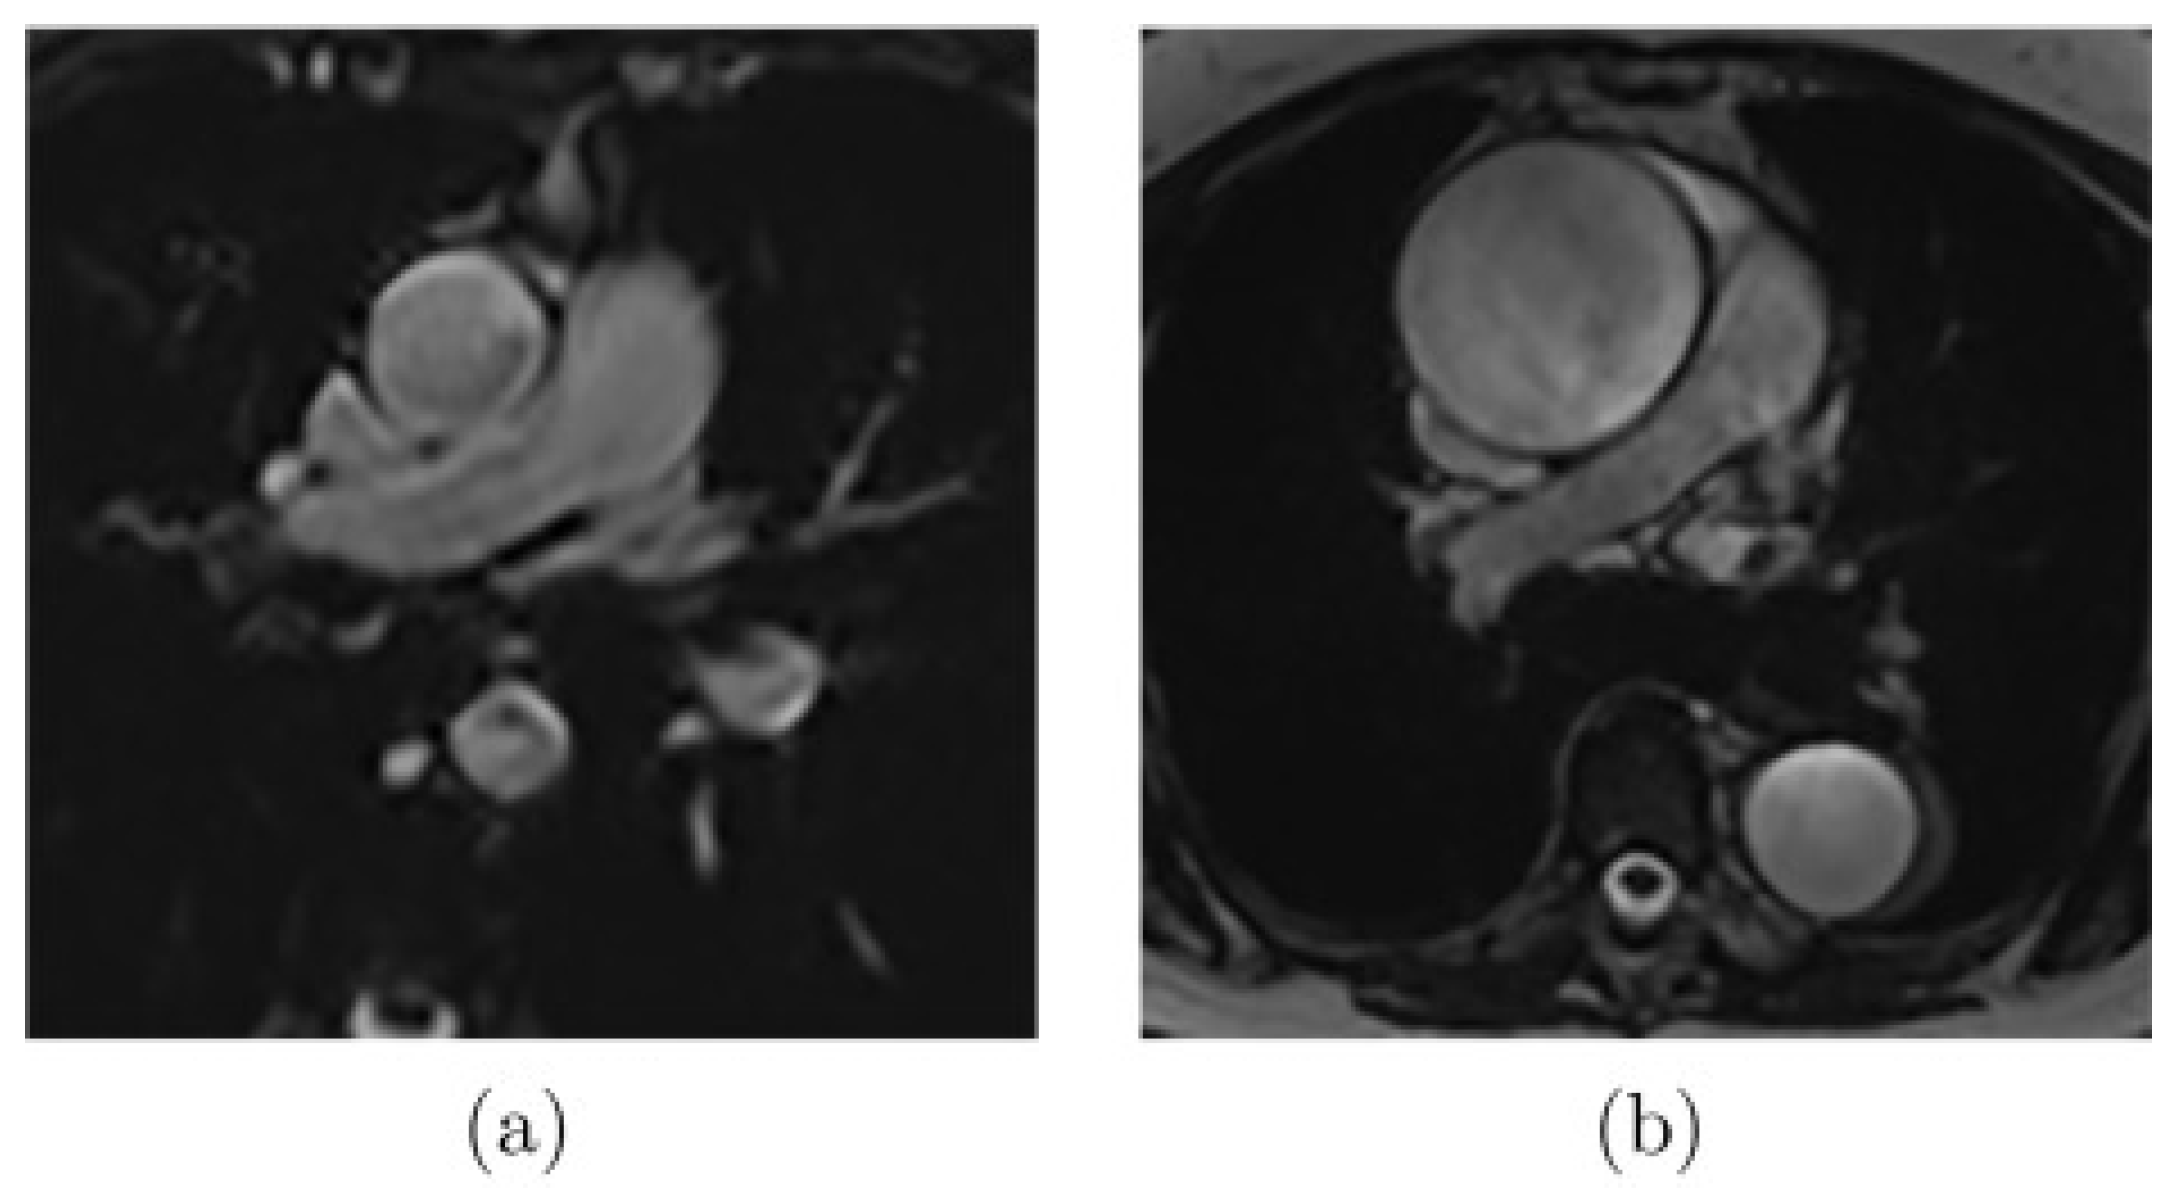

As presented in Figure 2, there are images where noise or artifacts are often present in the critical part of the cardiac cycle, especially for the ascending aorta, as the FLASH sequence is sensitive to rapid and turbulent flow. Another extreme case that complicates the segmentation (Figure 3a) appears when the aortic border is poorly visible due to the proximity of some other structures. Finally, other common difficulties can be encountered, such as the highly dilated ascending aorta as shown in Figure 3b.

Figure 3.

Examples of MR images where (a) the aortic wall is not well-defined due to the influence of the proximity of other structures or (b) the aorta is highly dilated [20].